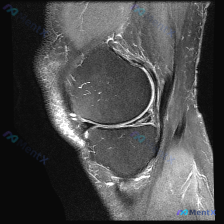

看到一个很有代表性的读片病例,怀疑半月板异常但单张T1加权MRI没有发现明确问题,整理了分析思路和大家分享。 病例核心信息 问题:临床怀疑半月板异常,提供单张膝关节矢状位T1加权MRI,需要做影像观察和分析 影像系统性观察结果 1. 骨性结构:股骨远端、胫骨近端、髌骨轮廓规整,骨髓信号正常,未见骨质...

给大家分享一个很有启发的膝关节MRI读片病例,临床关注点是半月板异常,读完片发现其实核心问题不在这儿,整理一下完整分析思路。 病例影像基本信息 这是一份膝关节矢状位T2加权MRI(压脂序列),我们先整理所有客观发现: 1. 关节内结构:半月板形态完整,呈典型低信号三角表现,未见贯穿性高信号,边缘光滑...